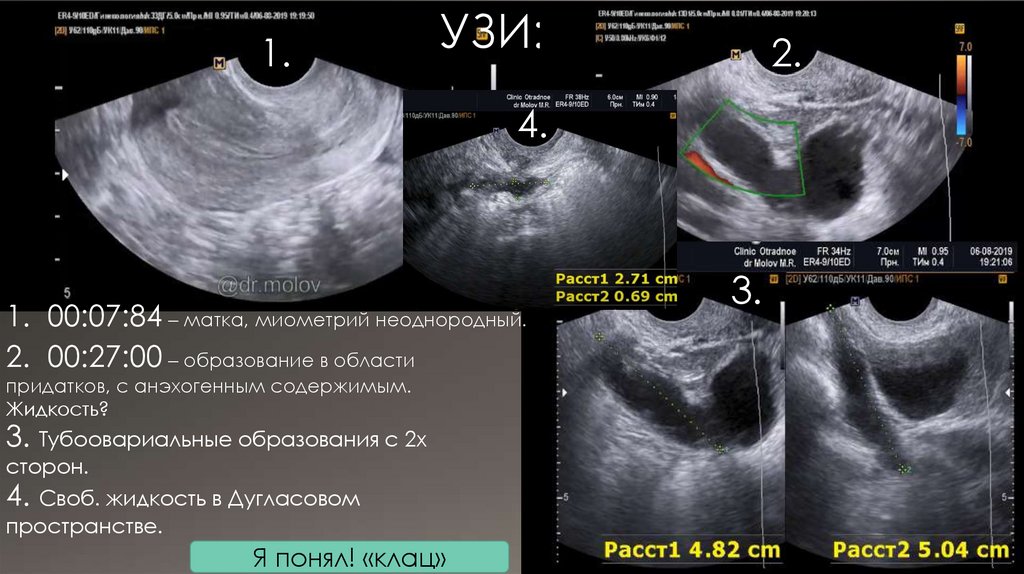

УЗИ:

2.

4.

1. 00:07:84 – матка, миометрий неоднородный.

2. 00:27:00 – образование в области

придатков, с анэхогенным содержимым.

Жидкость?

3. Тубоовариальные образования с 2х

сторон.

4. Своб. жидкость в Дугласовом

пространстве.

Я понял! «клац»

3.